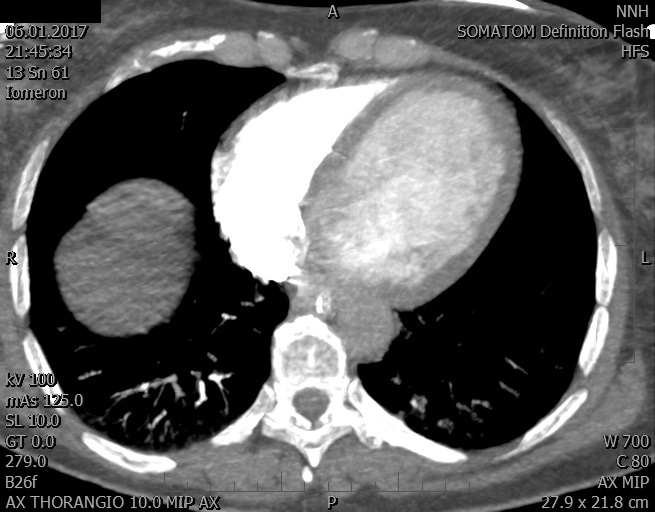

Video 2 - Echokardiograficky byla zjištěna těžká dysfunkce dilatační levé komory s nezvětšenou pravou komorou.Pro nejasnou příčinu zástavy jsme provedli i vyšetření výpočetní tomografií (CT), které vyloučilo plicní embolizaci (série 1 - soubory na konci článku). V den přijetí při přetrvávající oběhové nestabilitě byla nemocná opakovaně defibrilována pro fibrilaci komor se stabilizací rytmu po podání amiodaronu a mesocainu. Dle hemodynamických měření se jednalo o těžký kombinovaný šok. Vstupní laboratorní vyšetření bylo bez větších pozoruhodností. Posléze jsme doplnili anamnézu od příbuzných a zjistili, že pacientka užila do dvou hodin před srdeční zástavou první tabletu amoxicilinu na lehký respirační infekt. Při nevýtěžnosti vstupních vyšetření a nových anamnestických informacích jsme doplnili 14 hodin po kolapsu vyšetření koncentrace tryptázy v séru, která byla extrémně zvýšena (tabulka 2), což nás vedlo k podezření na anafylaxi.